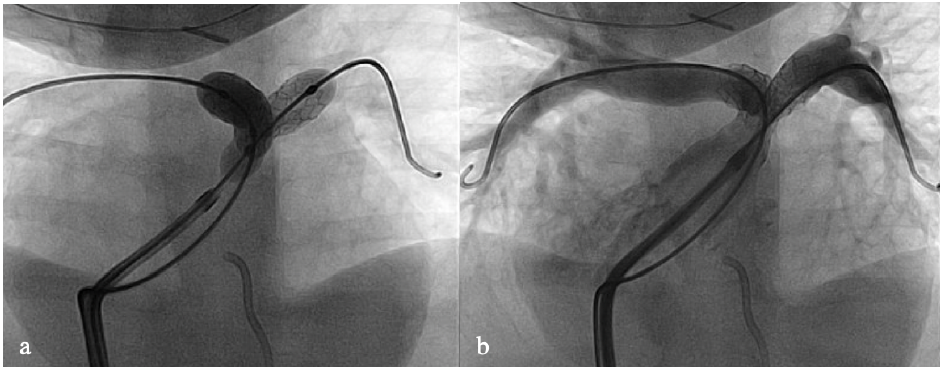

The technique for simultaneous stent placement has been described previously.8,10 In summary, 2 venous sheaths are placed, and hemodynamics and angiography are completed. Both areas of stenosis are crossed with catheters, then exchanged for stiff wires. Two appropriately sized stents are positioned across the stenotic areas from each venous sheath, then balloons are simultaneously inflated to deploy the stents. Alternatively, 1 stent is deployed initially, followed by simultaneous balloon inflation when the contralateral stent is placed. In both techniques, both balloons are simultaneously deflated in order to prevent deformation of the contralateral stent (Figure 1). Stents are further simultaneously balloon-dilated as needed. In cases where small-sized coronary stents are used, both stents may be placed through a single venous sheath.